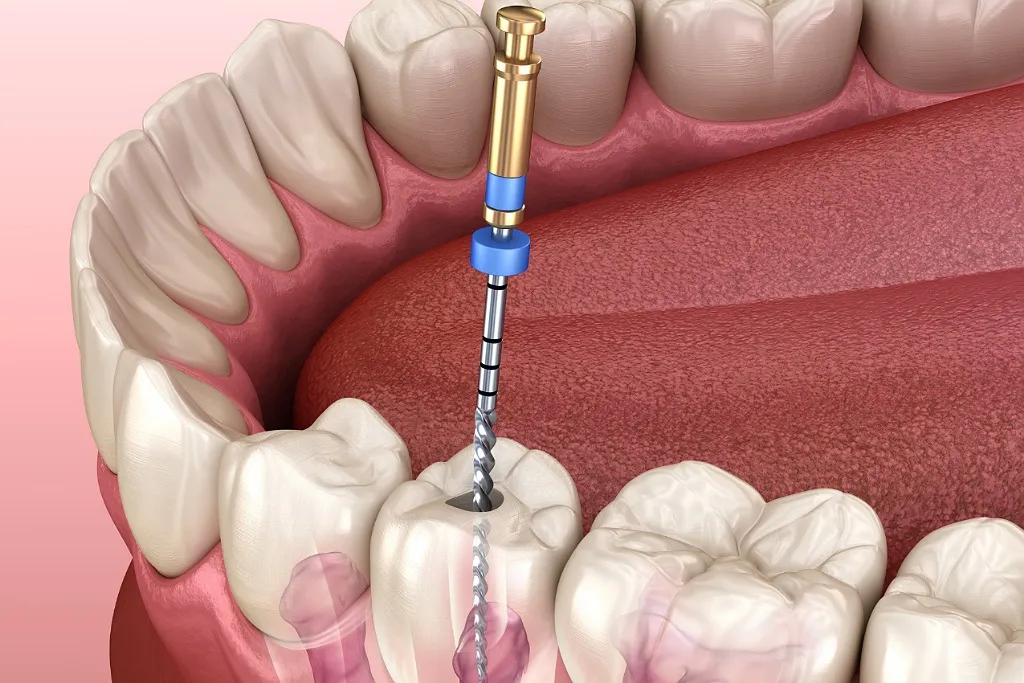

- باز کردن دندان: سوراخکردن سطح دندان برای دسترسی به کانال ریشه.

- تخلیه پالپ: برداشتن بافت عفونی یا آسیبدیده با ابزارهای دقیق.

- ضدعفونی کانال: شستوشو با مواد ضدباکتری و شکلدهی کانالها.

- پرکردن کانال: پر کردن ریشه با گوتاپرکا یا مواد مشابه برای جلوگیری از ورود باکتری.